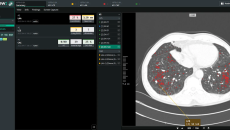

It joins Lunit and Us2.ai in the vendor-neutral, cloud-based marketplace of medical AI solutions.

Rad AI's genAI tools will be offered through Bayer's vendor-neutral Calantic Digital Solution marketplace, which provides AI-enabled clinical and operational applications.